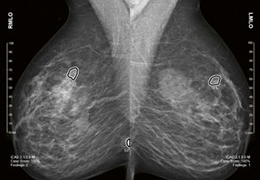

Eclipse 成像智能功能提供强大的处理能力和最佳质量的影像,同时减少质量错误并提高剂量效率。

凭借 AI、专有算法和先进的影像处理能力,提供出色的影像质量和无与伦比的诊断信心。

与标准影像处理相比,智能降噪功能可使客户降低辐射剂量,而不会损失影像质量。这在新生儿和儿科成像中尤其重要,在这种情况下以尽可能低的剂量成像至关重要。

提供相配视图选项,以减少所需的曝光次数,并提供更清晰的感兴趣区域视图。